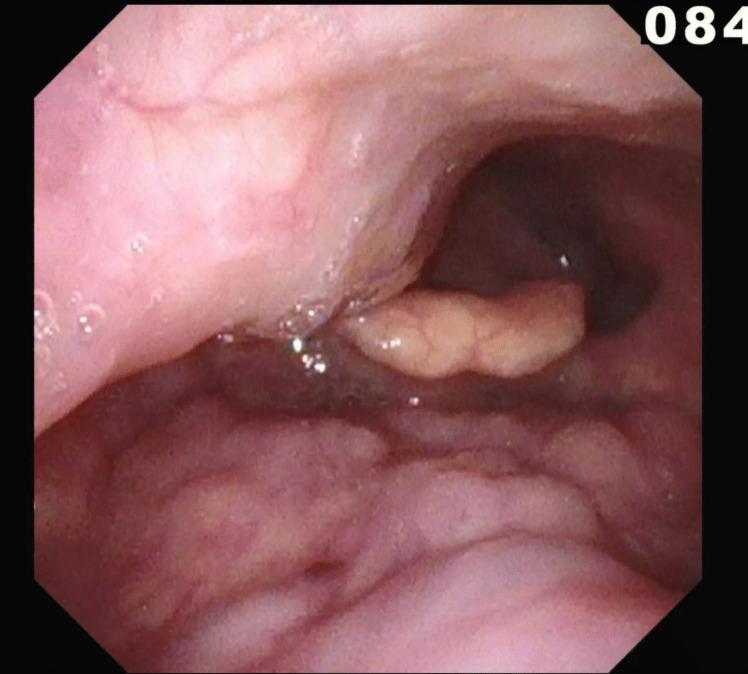

异常颈内动脉导致的吞咽困难:一例报告

Dysphagia from an aberrant internal carotid artery: a case report.

We present a case of dysphagia caused by an aberrant internal carotid artery (ICA). By reporting this rare occurrence, we hope to highlight the anomaly as a differential in cases of persistent, progressive dysphagia.

我们报告一例由异常颈内动脉(ICA)引起的吞咽困难病例。通过报告这一罕见病例,我们希望强调该异常情况可作为持续性、进行性吞咽困难病例的鉴别诊断之一。